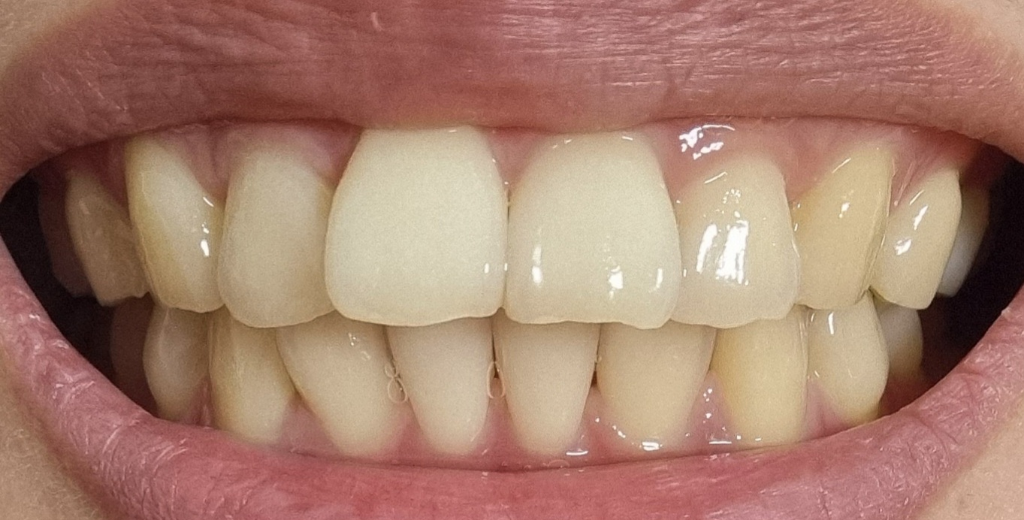

치아마모가 심한편인가요? 관리를 어떻게 해야할까요?

1. 치아 마모가 심각한 수준일까요?

• 1번 째 사진

사진상으로 보면 치아 마모상태가 심한거 같진 않습니다. 턱관절이 아프거나 그럴경우에는 스플린트나 보톡스 치료를 받으시면될것같습니다.

1. 사진상 치아 마모가 아주 심한 수준은 아니라고 판단됩니다.